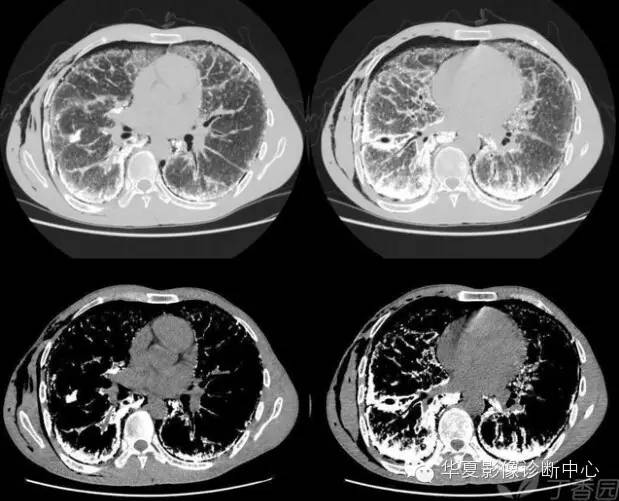

10、桃尖征 医学百科网 | YxBaike.Com

指肿块某一边缘尖角状突起形似桃尖,是肺炎性假瘤包膜的粘连牵拉,为良性肿块炎性假瘤特有。 医学百科网 | YxBaike.Com

医学百科网 | YxBaike.Com